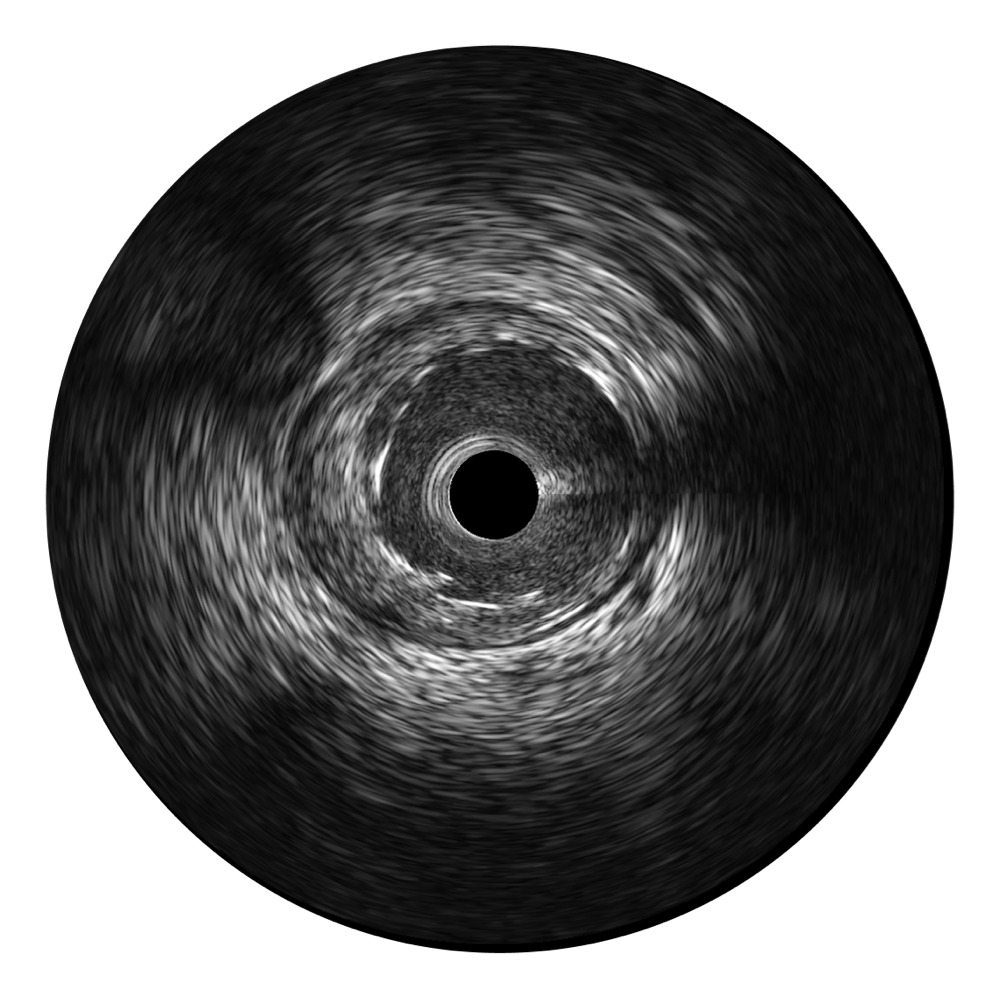

环球UG官网宽频IVUS图像

传统IVUS图像

对比传统IVUS导管成像,环球UG官网宽频IVUS图像的近场支架梁显影更细腻,远场中膜外血管仍清晰可辨,兼顾远中近,兼顾分辨力与穿透深度